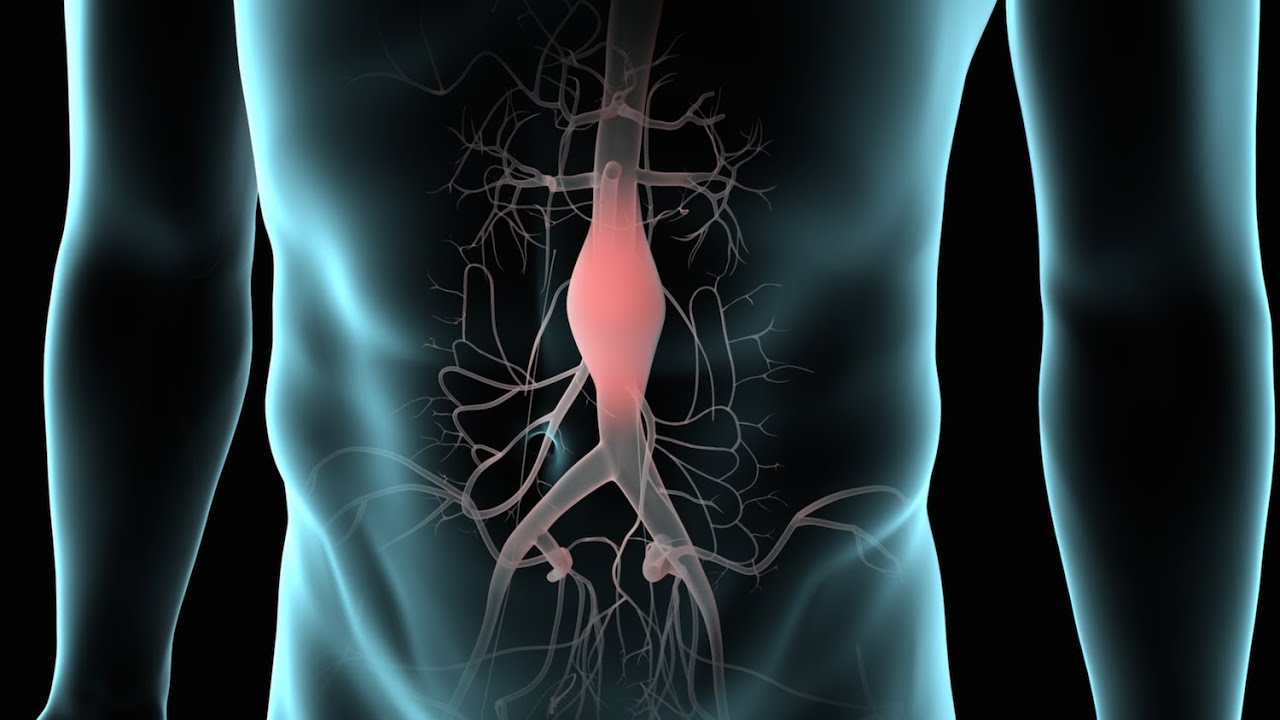

Un aneurisma aórtico abdominal es un agrandamiento de la parte baja de la aorta que se extiende a.

aneurisma de la aorta abdominal La aorta va desde el corazón hasta el. Recibe sangre con gran contenido en oxígeno. Cirugía vascularrupturas de aneurisma de la aorta abdominal: La cirugía de reparación abierta de aneurisma aórtico abdominal (aaa) se realiza para arreglar una parte dilatada de la aorta. Si tienes un aneurisma de la aorta abdominal en expansión, podrías notar lo siguiente: La incidencia de aaai en. En este artículo examen físico pruebas de detección y de diagnóstico ¿quiénes deben someterse a un examen de detección de aneurisma de aorta torácica? Los aneurismas aórticos aneurismas aórticos la aorta, que mide alrededor de 2,5 cm de calibre o diámetro, es la arteria más grande del cuerpo.

Aneurisma aórtico abdominal localización y apariencia. 2022

Source: www.deperu.com